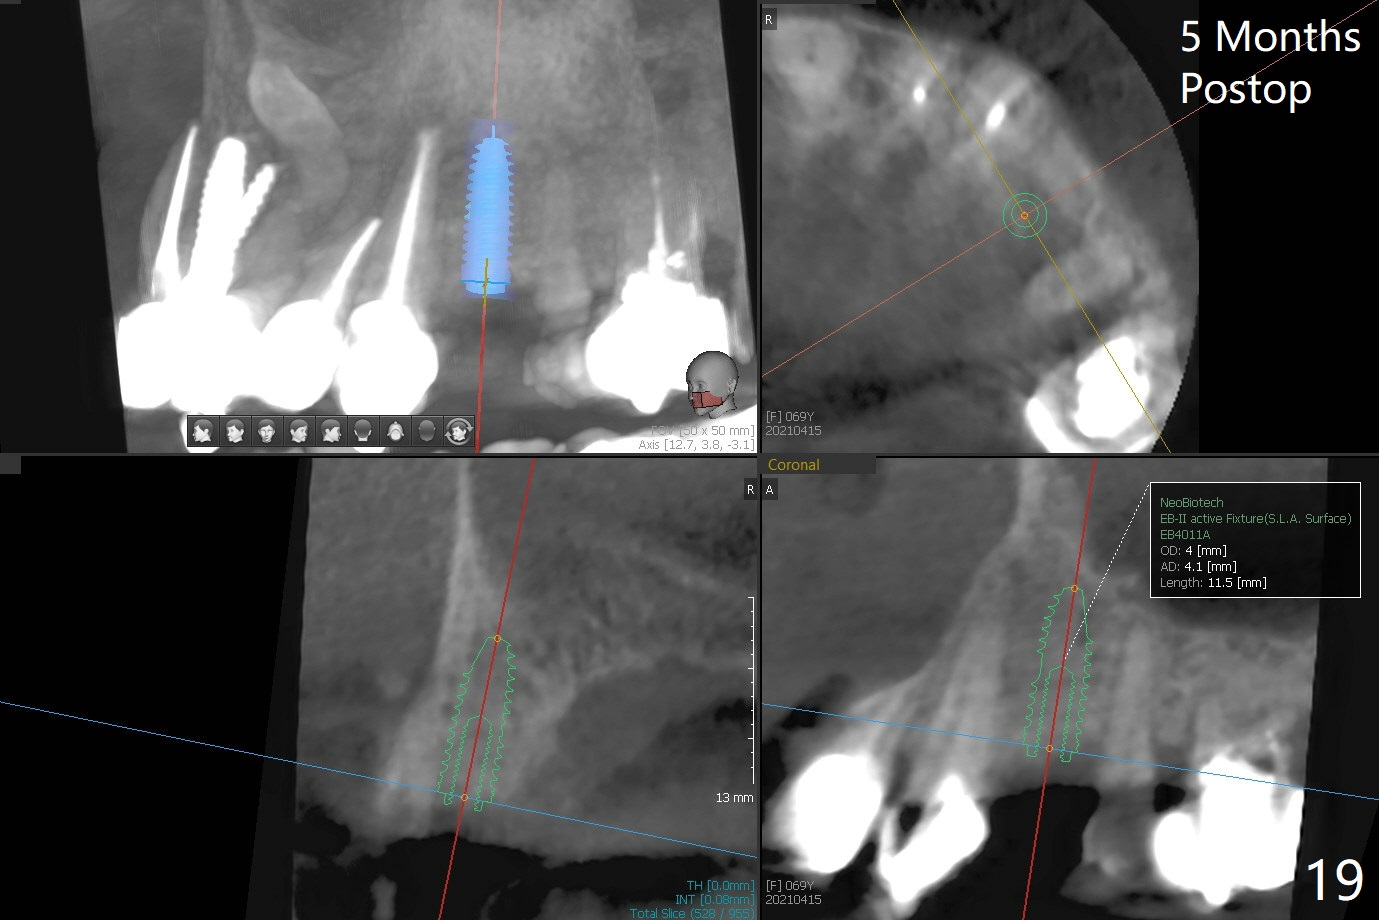

68岁女左上4颊侧瘘道(图一:*),与根尖颊侧骨板缺失相通,其实腭侧根尖周围病变更大(也与颊侧窝相通),术中没有注意腭侧根接近3(图二:P),稀里糊涂的基本顺着腭侧根(颊侧)走向钻洞(图四,与图三理想方向对比),突然记起术前设计钻洞必须在腭侧牙槽窝远中颊侧,在远中建立新洞眼(图五),之后无法再次建立新洞眼,只好利用同一个侧面切割钻头将钻洞往远中移位,同样效果不佳(图六),最后只好放弃,放置粘性骨粉(图七:*),覆盖PRF膜,6个月胶原膜,PGA缝线,牙周胶水。术后重新分析表明顺着腭侧牙槽窝种植与尖牙还是有分离(图八,九:*),因为牙槽窝是斜型的(图十:黑色),不过离颊侧骨板也接近(图八:B)。所以钻洞必须斜型针对远中骨壁,表浅些(图十一:红色箭头);一旦进入骨板,改变角度(图十二:红色箭头),适当矫枉过正,随着植体增大,钻洞会往近中偏移(白色箭头)。最好植体方向理想(图十三)。不过植骨后钻洞偏移可能性比较少。缝线和牙周胶水似乎是一个稳妥固定胶原膜方法。术后病人抱怨水肿严重,术后八天颊侧根尖隆起是由于骨粉推出骨板之外(图十五,十六:*),上颌窦底板无意穿孔(^)伴有上颌窦膜(M)增厚,与术前对比(图十七:上颌窦窦腔清晰)。术后一个月6个月吸收膜不见了,大多数缝线已经脱落,最后两根缝线撤除后,牙槽窝开口已经关闭,好像主要成分是骨粉(图十八)。术后5个月牙槽嵴宽,角化龈也宽,好像可以植入4x11.5毫米植体(图十九)。